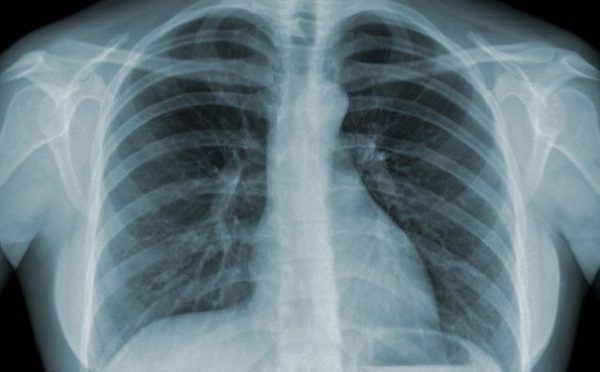

Chụp X quang phổi

- Biểu hiện cận lâm sàng của bệnh viêm phế quản mạn tính qua phim chụp X-quang. (ảnh minh họa)

Việc chụp X quang phổi là rất cần thiết giúp loại trừ các căn nguyên ho kéo dài do các bệnh có tổn thương ở nhu mô phổi (lao phổi, ung thư phổi, viêm phổi kẽ …) hoặc các bệnh lý phế quản như giãn phế quản …